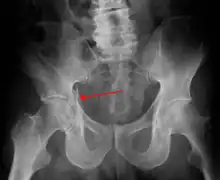

| Acetabular fracture as seen on plain X-ray |